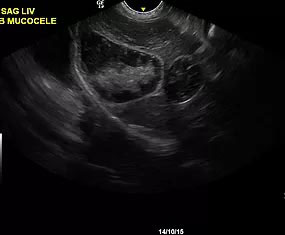

We elected to offer not only abdominal, cardiac and small parts ultrasound but also provide interventional procedures necessary to fulfill the diagnostic pathway. By doing so, we are capable of scanning a patient, working with attending veterinarians to assess patients for biopsy or aspiration and then collecting any samples that may be required to accurately diagnose and address the underlying concern.

At RVUS we have chosen industry leading equipment from vendors with reputable and proven track records in the industry. From the front lines to your final report it is imperative that the equipment and the user provide images that equip the specialists with the highest level of quality and reproducibility to confidently provide an accurate interpretation of the sonogram.

This, in turn, provides you with additional tools to arrive at a diagnosis and prognosis and to enhance the care model for your patient and confidence with your client. Our team of professionals with decades of ultrasound experience encourage the use of ultrasound as a leading route to non-invasively assess organs and pathology in question. To cover that spectrum, a variety of transducers are essential, all with different characteristics.

Whether your patient is 100 lbs or 10 lbs, take comfort in knowing your sonographer is capable of generating images that are sensitive and specific to the clinical concerns.